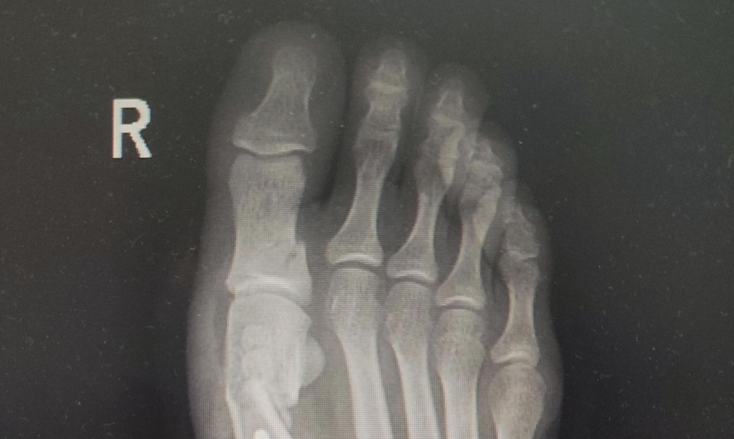

观察女死者尸表时,她的大脚趾的特异性变形情况,引起了法医的特别注意!

这名女死者的双脚五指有明显的并拢倾向,除此外她还有明显的骨盆前倾征象。

根据法医的观察经验,他判断这名女死者是长期穿高跟鞋走路导致的身体畸变。

图文无关,仅为示意图。穿高跟鞋导致脚部异变的病症示例,图源:百家号。

因此,她应该也是有钱家庭出身的女性。因为在1995年,虽然很多女性开始爱穿高跟鞋,但并不经常穿。如此严重的身体畸变,证明这位女性爱穿高跟鞋的习惯,至少延续了十年,或许少女时期她就开始爱穿高跟鞋,这才导致身体异变明显。